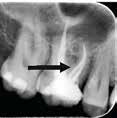

Fig. 8. Skematisk illustration af (A) en præmolar med 30º lingval kipning (18). Bor viser potentielt område for perforation (B) præmolar med 30º rotation (C) underkæbeincisiv med let/moderat kipning af roden, men overkontureret krone. Bor viser potentielt område for perforation. D. præmolar med distal kipning og molar med mesial kipning. Bor viser potentielt område for perforationer (18). E. Røntgenoptagelse af molar med let til moderat mesial kipning; bor viser perforationsområde.

F. Røntgenoptagelse af tand med mesialt placeret oplukningskavitet og fremmedlegeme i alveoleknoglen som følge af perforation.

Fig. 8. Schematic illustration of (A) a premolar with 30º lingual tilt (18). Bur showing potential area of perforation (B) premolar with a 30º rotation (C) lower incisor with a mild/moderate tilt in the root but an over-contoured crown. Bur showing potential area of perforation. D. premolar with distal tilt and molar with mesial tilt. Bur showing potential area of perforations (18). E. Radiograph showing a molar with a mild to moderate mesial tilt with bur showing area of perforation. F. Radiograph of tooth with mesially placed access cavity preparation and foreign material lodged in the alveolar bone due to perforation.

En tandlæge i Kategori A har ikke erhvervet tilstrækkelige færdigheder til at kunne modificere oplukningskavitetens udformning i en tand, der er kippet eller roteret. For at undgå unødvendige uheld som perforation i forbindelse med oplukningen (Fig. 8A-F) bør sådanne tænder kun behandles af tandlæger, der mindst er i Kategori B.